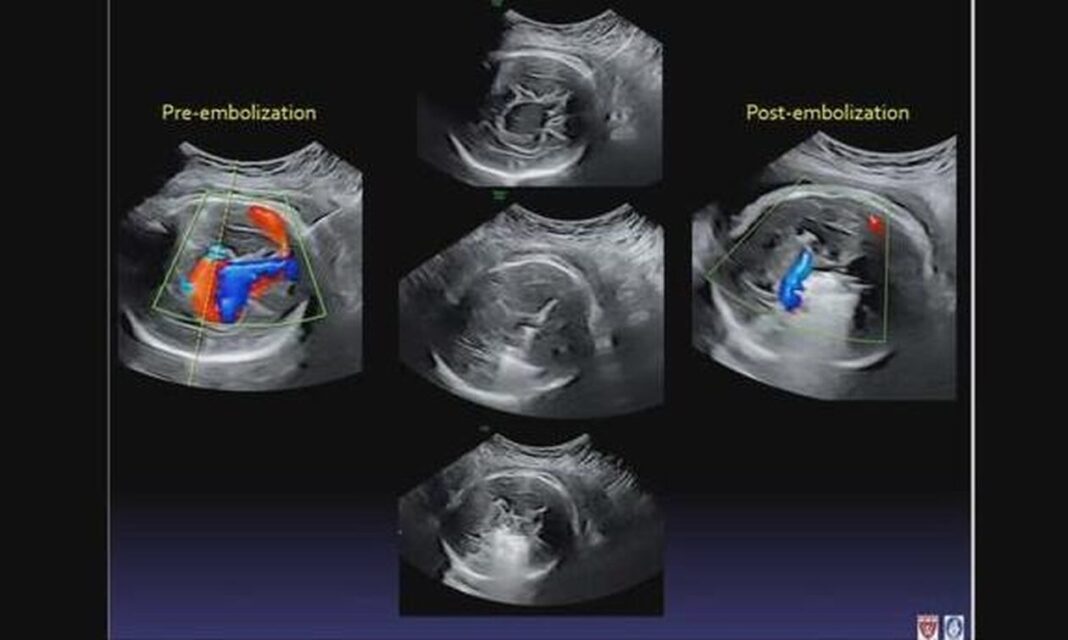

Από εκεί, οι γιατροί εισήγαγαν μια βελόνα μέσω του κοιλιακού τοιχώματος, περνώντας προσεκτικά έναν καθετήρα μέσω της βελόνας, έτσι ώστε οι μικροσκοπικές μεταλλικές σπείρες να γεμίσουν τη φλέβα, να επιβραδύνουν τη ροή του αίματος και να μειώσουν την πίεση.

Το μωρό έδειξε σημάδια βελτίωσης αμέσως, με τις σαρώσεις να δείχνουν μειωμένη αρτηριακή πίεση σε βασικές περιοχές.

«Ήταν συναρπαστικό αυτή τη στιγμή που είχαμε τεχνική επιτυχία στο να κάνουμε τον εμβολισμό», είπε ο Orbach.